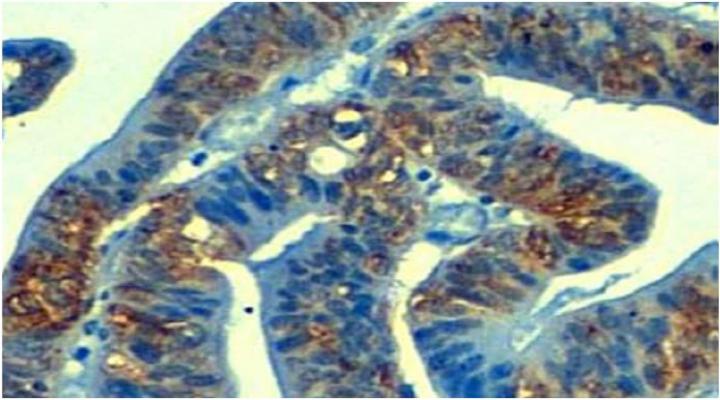

"We have found that 10% of colon and stomach tumors present the loss of a molecule called TP53TG1, whose function in healthy cells is to prevent activation of YBX1 protein. Without surveillance of TP53TG1 in these gastrointestinal tumors, YBX1 goes to the nucleus of the cell and is responsible for the activation of hundreds of oncogenes that will prevent the death of malignant cells that antitumor drugs induce", says Dr. Manel Esteller.